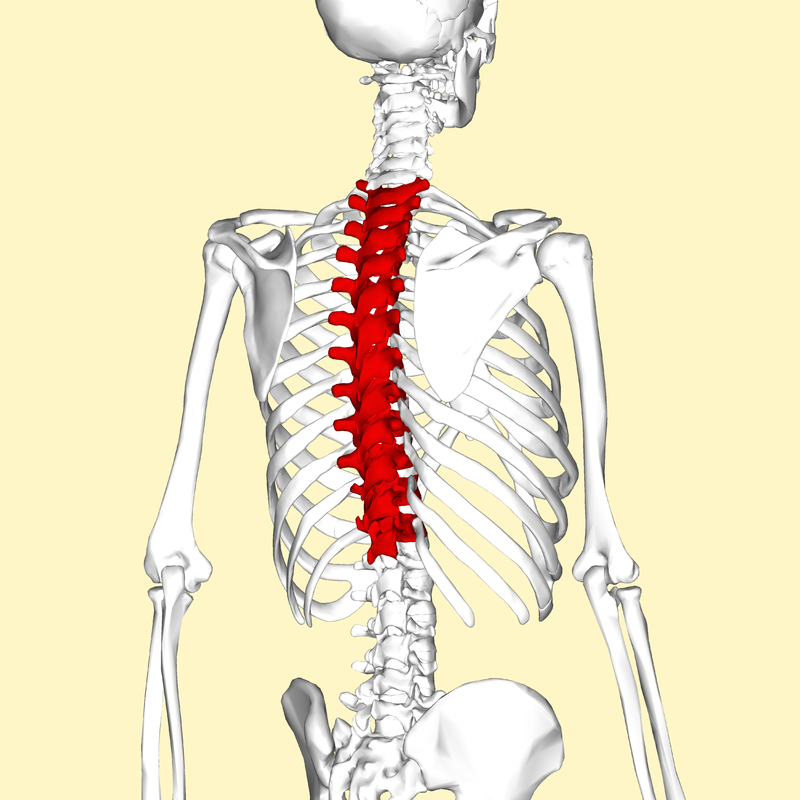

흉추(thoracic vertebra)

경추(목뼈)와 요추(허리뼈) 사이에 위치하여 척주의 중간 부위. 12개의 추골(T1-T12)로 이루어져있으며 아래쪽으로 갈수록 크기가 증가한다.

https://en.wikipedia.org/wiki/Thoracic_vertebrae